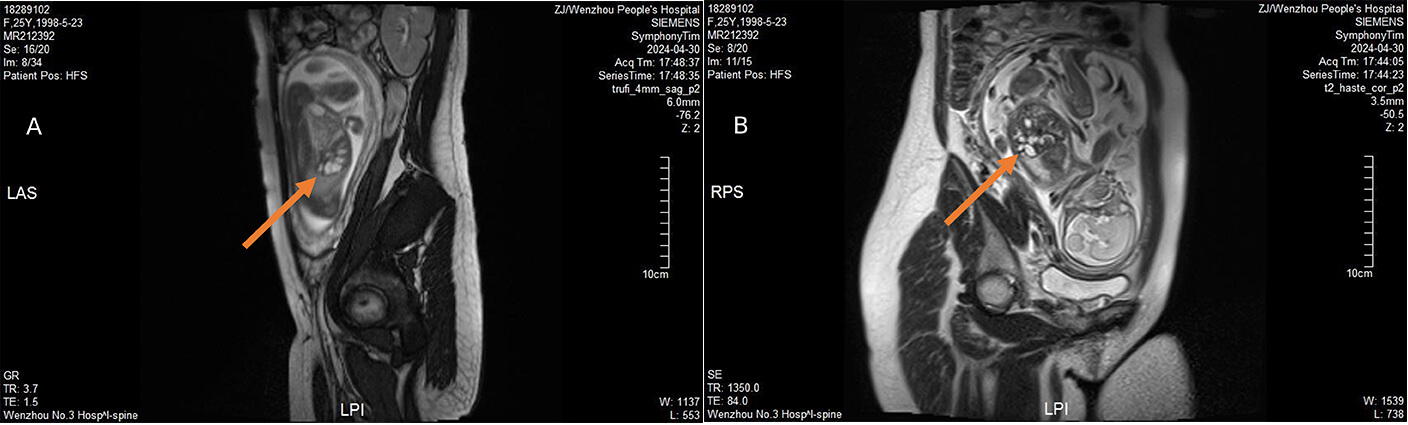

Fetal MRI performed the same week (1.5-T Siemens; predominantly T2-weighted sequences) confirmed ill-defined hilar bile duct structures and diffuse intrahepatic ductal dilatation. The kidneys, bladder, and intestines were normal, with preserved corticomedullary differentiation and no nephromegaly (Fig. 2). The concordant imaging findings supported a ductal-plate malformation within the Caroli spectrum and prompted invasive genetic testing.

Fig. 2.

Fetal MRI findings. (A) MRI shows an ill-defined hilar bile duct (indicated by the orange arrow). (B) MRI reveals dilated intrahepatic bile ducts (indicated by the orange arrow), with no other significant abnormalities detected. Images are de-identified. MRI, magnetic resonance imaging.